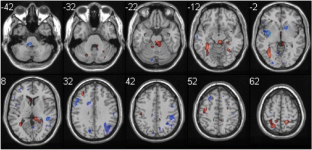

Restoration of motor function following stroke involves reorganization of motor output through intact pathways, with compensatory brain activity likely variable by task. One class of motor tasks, those involved in self-care, is particularly important in stroke rehabilitation. Identifying the brain areas that are engaged in self-care and how they reorganize after stroke may enable development of more effective rehabilitation strategies. We piloted a paradigm for functional MRI assessment of self-care activity. In two groups, young adults and older adults, two self-care tasks (buttoning and zipping) produce activation similar to a bimanual tapping task, with bilateral activation of primary and secondary motor cortices, primary sensory cortex, and cerebellum. Quantitative differences include more activation of sensorimotor cortex and cerebellum in buttoning than bimanual tapping. Pilot subjects with stroke showed greater superior parietal activity across tasks than controls, potentially representing an increased need for sensorimotor integration to perform motor tasks.

Fig. 1